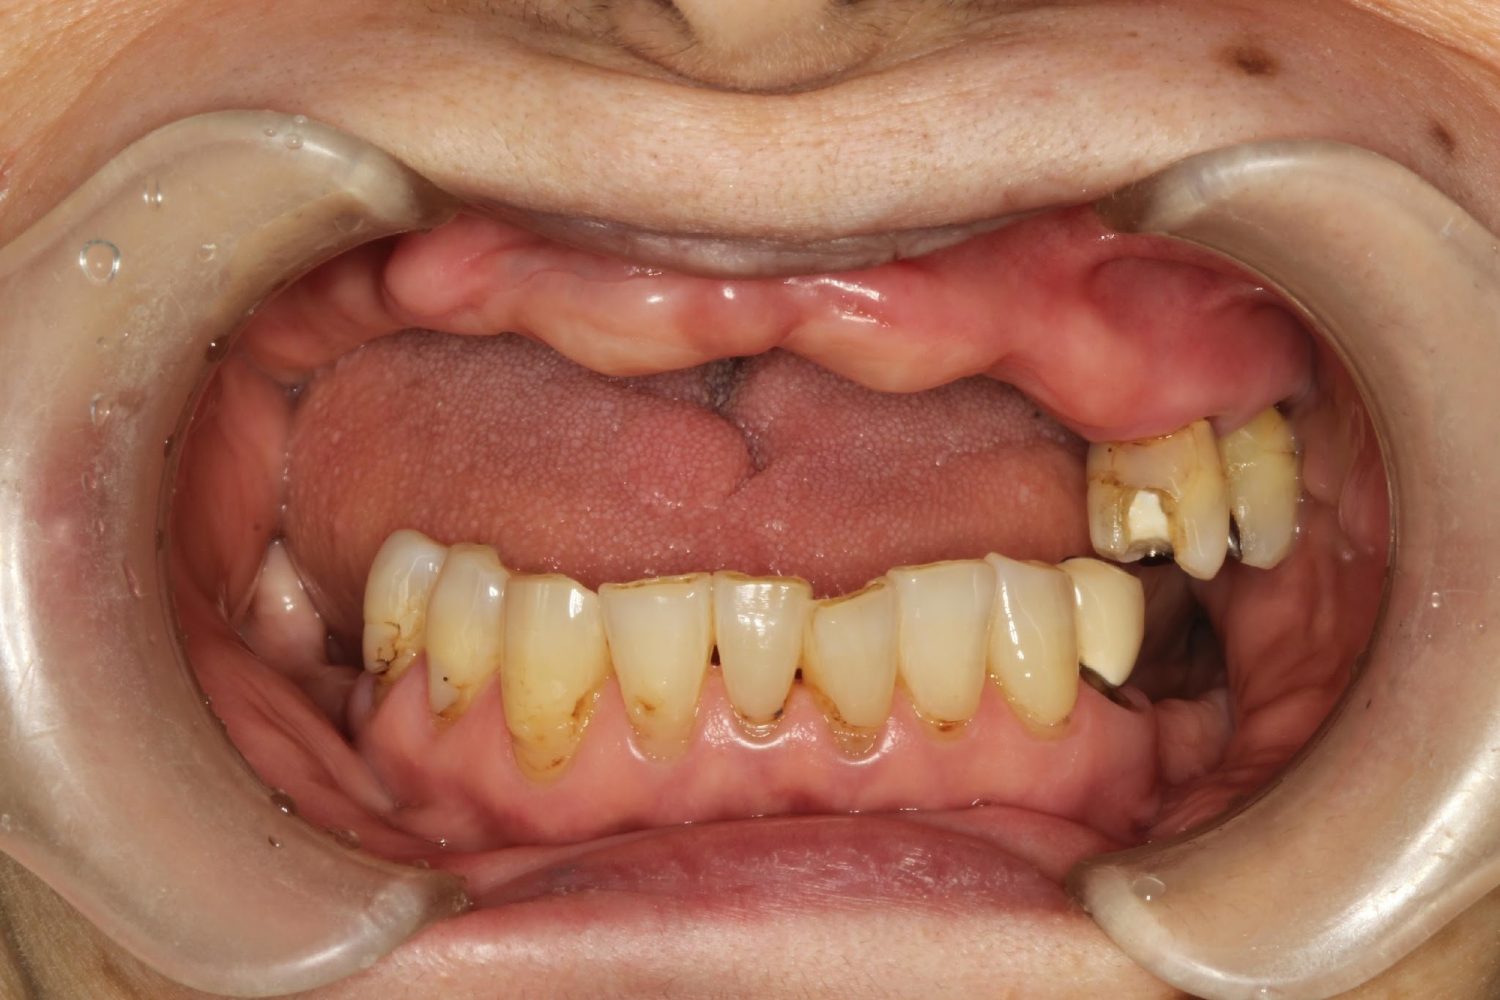

インプラント治療の症例紹介③

Before

After

主訴

むし歯の治療

治療内容

保存不可能な歯の抜歯

下顎にインプラント埋入し咬合再構成

治療費

2,688,400円(税込)

治療期間

14か月

治療回数

21回

想定されたリスク

※上部構造の形態が複雑になるため清掃が難しくなる。インプラント周囲炎の恐れがありました。

多数歯う蝕および多数歯欠損による咬合崩壊、保存不可能な歯の抜歯により上下無歯顎に。下顎に6本インプラント埋入する事で咬合再構成を行った。